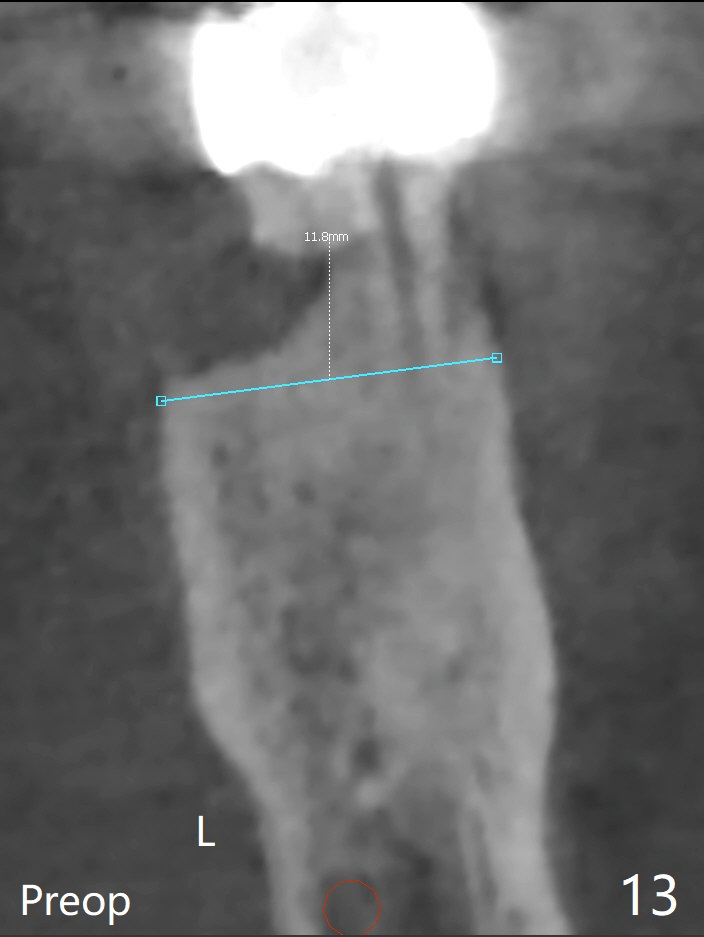

A 54-year-old man has distal (D) root fracture at #19 while the implant at #2 is osteointegrarting (Fig.1,2). Because of the large distal defect (Fig.3, after extraction), osteotomy (red line) will be initiated in the mesial socket (Fig.4, as distal as possible, with the coronal end in the middle of the socket) or the mesial slope of the septum (Fig.5) so that the implant (green) will be supported by the distally displaced septum (Fig.6 arrow). CT taken 8 months later confirms distal root fracture. A 6x11.5 mm or longer implant seems to be appropriate for the site (Fig.7). Three years later there is severe buccal swelling (Fig.8) with vertical mesial and distal root fractures (Fig.9). Although the buccal plate is lost, the septum remains (Fig.10 S), which will provide with blood supply to the bone graft (Fig.11), covered with Bioxclude and 6-month membrane and PSA suture. The bone density in the mesial and distal sockets is higher than that in the septum 8 months post cortical bone graft (Fig.12). In spite of bone graft, the buccolingual width reduces by almost 4 mm 8 months post extraction (Fig.3,4). In spite of bone graft, the buccolingual width reduces by almost 4 mm in 8 months post extraction (Fig.3,4). A 5x11.5 mm implant will be placed (Fig.15).